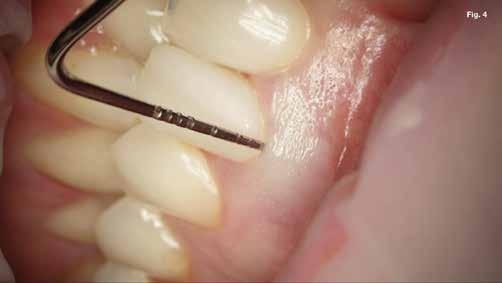

Szépen beállított ideiglenes korona volt jelen, kóros szondázási mélység és szondázási vérzés nélkül. Nem volt jelen sinus tractus (3–5. ábra). Tüneti apikális parodontitis 1. osztály (Von Arx&Cochrane 2001); B osztály (Kim&Kratchman 2005) és korábban elvégzett gyökérkezelés volt a végső diagnózis.

A kezdeti konzultáció során az LL6 nem reagált az Endo-Frost (COLTENE) és az Electric Pulp testerrel végzett érzékenységi vizsgálatokra, és ütögetésre érzékenynek bizonyult. Bukkálisan a lágyrészekhez kapcsolódó fisztulát észleltek, és tapintásra némi érzékenységet, míg a fogak mozgékonysága a normális határokon belül volt. A műtét előtt készült periapikális röntgenfelvételen az LL6 gyökereihez kapcsolódó periradikuláris röntgenfelvételek voltak láthatóak (1. ábra).